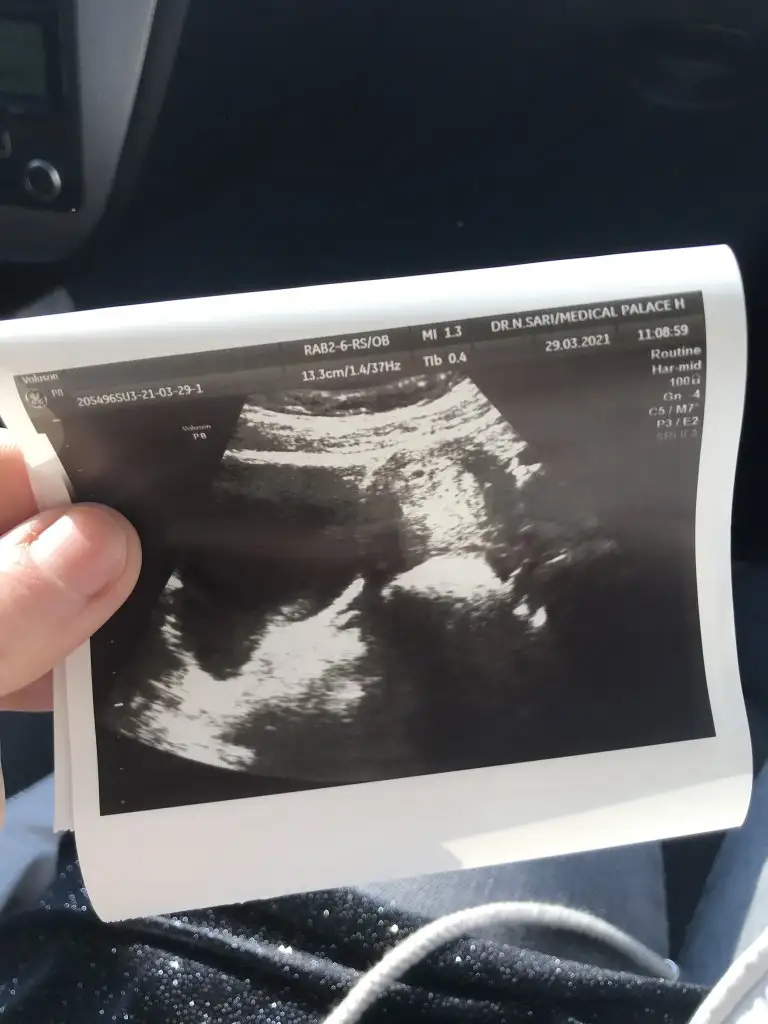

Bana da bakar mısınız? 6+4 burda

Eklentiler

• 16175398671275371102888315156871.webp

16175398671275371102888315156871.webp

19,3 KB · Görüntüleme: 77